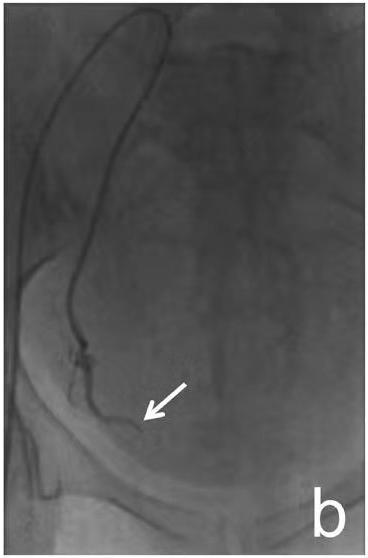

诊断支气管扩张30年,咯血两周。造影发现左右侧支气管动脉迂曲扩张。

治疗前

介入栓塞后,支气管动脉不再向肺内供血,咯血停止。

治疗后